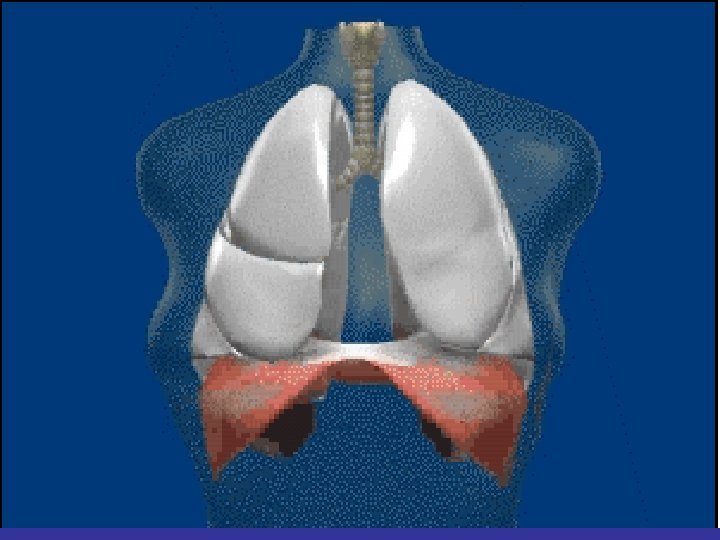

Lobes and Fissures